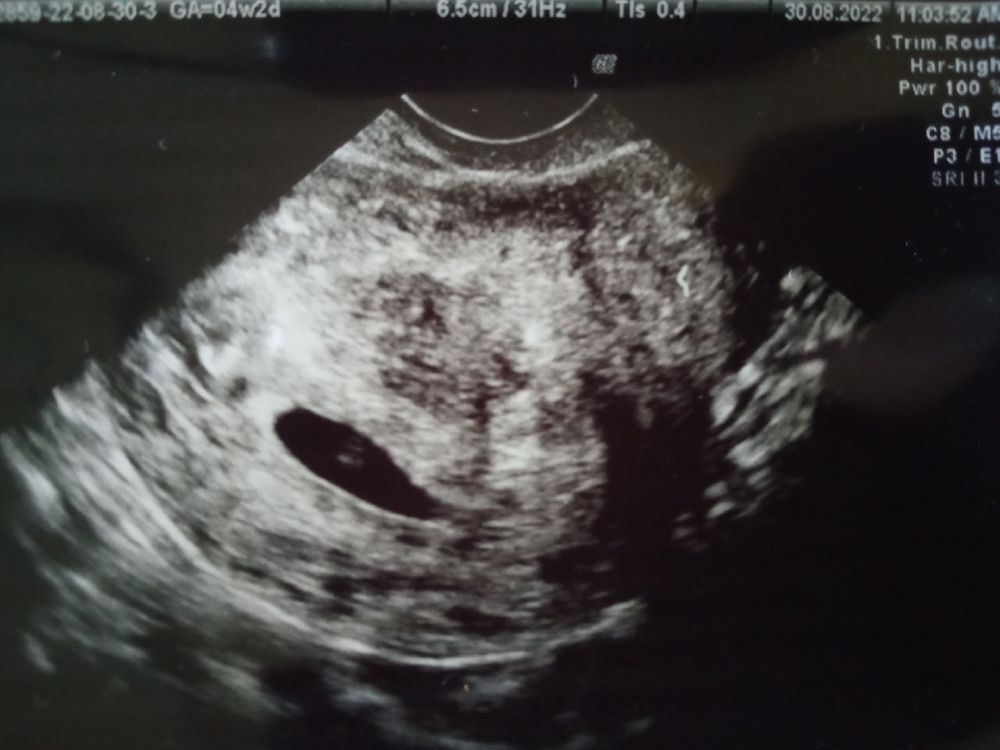

Первое УЗИ ✅

УЗИ, КТГ, доплерВчера (акушерских 4 и 2) очень сильно болел бок справа. Вот прям очень. Отдавало в ногу, в спину. Конечно, почитала про внематочную, попугалась.

Поэтому поехала утром на УЗИ.

Болит жёлтое тело (возможно, неправильно выразилась, но это всё оно!), это бывает, отсюда и огромная болезненная грудь, и тошнилки (которых у меня кроме как в машине и нет). Вообще врач сказала, что и матка может побаливать, растягиваясь, и это, все мы знаем, норма. Наказала расслабиться, лопать витаминки и приходить через неделю-две слушать сердцебиение.

Из прикольного: при акушерском сроке в четыре недели беременность развивается на пять. Врач говорит - бывает, из-за моей ранней овуляции и короткого цикла.

Очень рада, отлегло. Мой котёнок на месте.